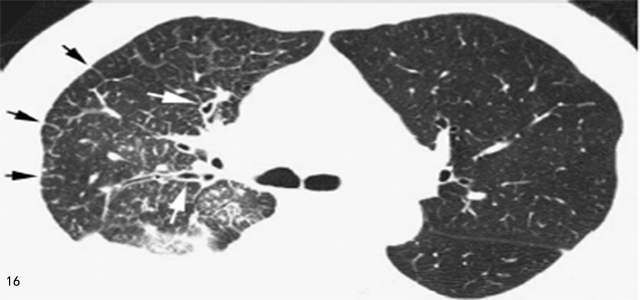

3. 癌性淋巴管炎

平片的典型表现为单侧或不对称的肺间质增生伴KerleyB 线,但常见不典型表现。高分辨率CT 常显示小叶间隔增厚(图16),支气管血管周围间质增厚和叶间裂增厚。

图16 肺癌的淋巴管播散

高分辨率CT 显示单侧的小叶间隔(黑箭头) 增厚和支气管血管周围的间质(白箭头) 增厚,右侧胸腔可见积液